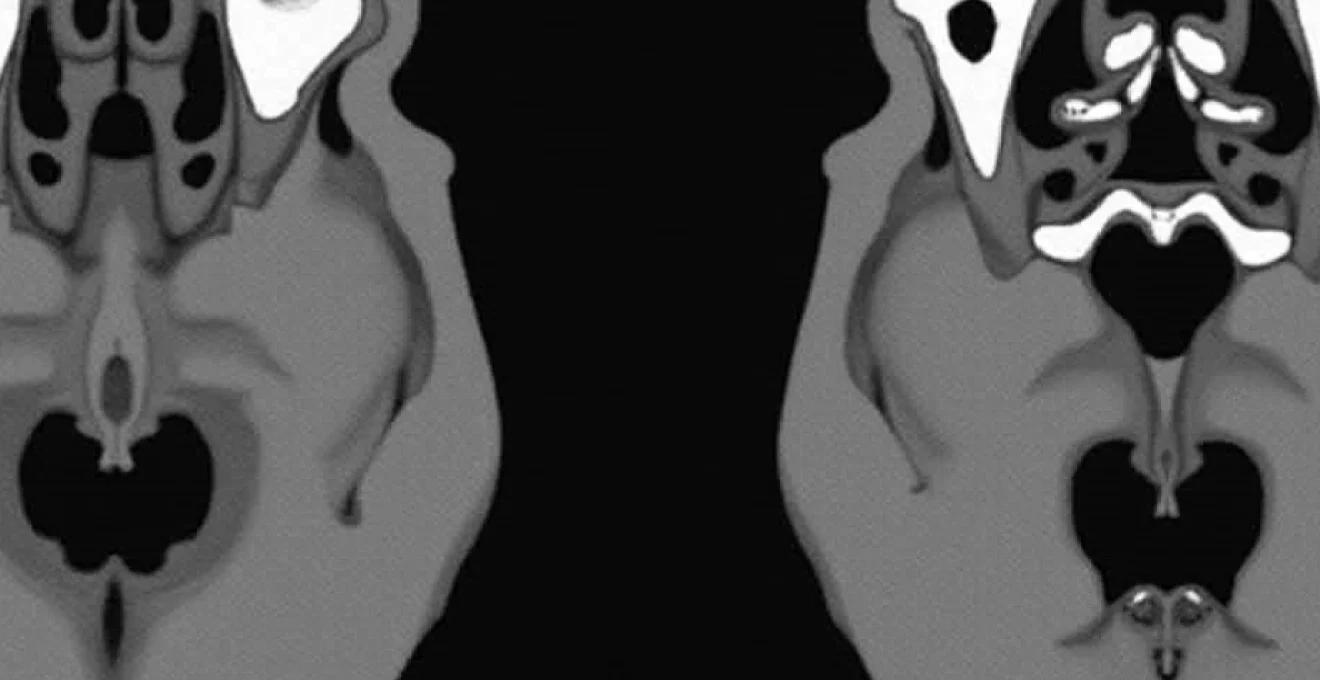

CT myelography protocol for neural foraminal stenosis evaluation

CT myelography remains an invaluable tool for assessing neural foraminal stenosis in cases where MRI findings are equivocal or when precise bony detail is required for surgical planning. This technique combines the excellent bony resolution of CT with contrast enhancement of neural structures, allowing for detailed assessment of both soft tissue and osseous contributions to neural compression. The procedure involves intrathecal contrast injection followed by CT imaging in multiple positions, providing dynamic information about neural compression patterns.

For C5-6 and C6-7 disc osteophyte complexes, CT myelography can precisely delineate the degree of foraminal narrowing and identify the specific anatomical structures responsible for nerve root compression. The technique is particularly valuable in distinguishing between anterior osteophytic compression and lateral disc herniation, information that directly impacts surgical approach selection. Three-dimensional reconstructions from CT myelography data can provide surgeons with detailed anatomical roadmaps, particularly useful in complex cases involving multilevel pathology or previous surgical intervention.